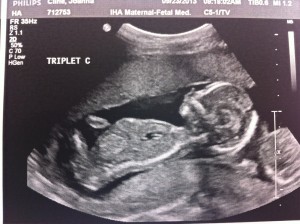

Hello!! I’m 16 weeks today and it was the BIG appointment where we learned the sex of the fetuses!!

Baby A – is a BOY!

Baby B – is a GIRL!

Baby C – is a BOY!

A is 170 grams, B is 175 grams and C is 178 grams so they’re all measuring well. Grow, grow, grow!